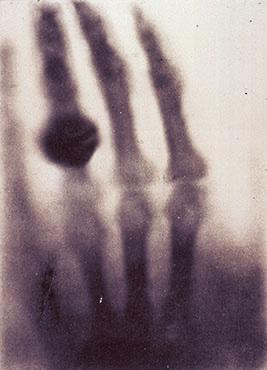

With jittering excitement, Roentgen began attempting to stop the rays by placing various objects around his laboratory between the cathode tube and the screen: a book, different metals, and eventually his own hand. He saw shadows of his bones. He noted the varying penetration of the X-rays through materials. A few weeks after his initial discovery, he used his crude X-ray machine to photograph his wife Anna Bertha’s hand. “I have seen my death!” Anna exclaimed as she viewed the picture— the first radiograph (fig. 2). The famous image of Anna’s hand with the outline of her wedding ring has since been immortalized in medical history.

Cathode rays are the the flow of electrons emitted from a negatively charged electrode when voltage is applied in a vacuum environment (i.e. a vacuum tube). Numerous vacuum tube models, collectively known as cathode tubes, were created to evoke cathode rays, producing varying amounts of photoelectric effect that could be captured on a photoluminescent screen up to 8cm away from the cathode. He initially conducted his experiments using Lenard tubes, which allowed the cathode rays to exit through a small window in a thin sheet of aluminum foil, captured on a phosphor screen placed at the end of the tube. When Roentgen was initially experimenting, he held the phosphor screen very close to the window through the aluminum sheet, and the results were minimal. He decided instead that the Crookes-Hittorf tube, which utilizes thick glass at the area of focused cathode rays, would result in a higher magnitude and a more noticeable phosphorescent effect on the screen. He then attached a Ruhmkorff induction coil to maximize the electron velocity, releasing an electrostatic charge of up to 20,000 volts per pulse, yet the results were still minimal. He then covered the outside of the tube in cardboard cover in black paint, to stop cathode rays from escaping sideways, focusing all the electrons through the thick glass end of the tube, onto the phosphor screen—the results were still minimal. There was some luminescence, but nothing other scientists had yet prove.

Then, whether he was leaving from his usual Friday late night experiments, or purposely trying to limit the confounding visible light, he blew out all his candles. That’s when he noticed: another screen, on another lab bench, far away from the tube, a screen coated in barium platinocyanide, was glowing. Given the screen's distance compared to the tube, he knew these could not be the cathode rays. The black, non-conductive cardboard blocked visible light from leaving the sides of the tube and the lab was completely dark. Roentgen concluded the rays causing the fluorescence on the screen could not be from rays with wavelengths within the visible spectrum. The type of ray he just observed was unknown. Roentgen named these strange rays X-rays, X for “unknown.” Whether it was fate or a lucky break, on Friday, November 8th, 1895, Roentgen created the perfect formula of confounding variables that allowed him to notice and discover X-rays, changing his

Roentgen’s legacy constitutes one of the most significant discoveries in the field of medicine that ignited exponential change in healthcare. From modest beginnings of incidental discoveries, radiology has become a cornerstone of modern medicine, blossoming into an integral role in the patient care continuum. From the radiograph exhibiting Anna Bertha’s wedding ring, to the clarity of today’s imaging technologies like MRI and CT, and the future of photon counting CT and virtual reality imaging assessments, Roentgen’s observation is celebrated as leaving a magnificent legacy in medicine and the overall advancement of humanity, biology, and physics.